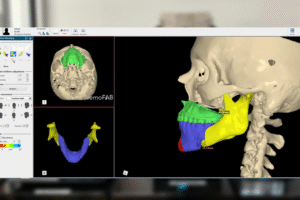

3D Printing in Healthcare has transformed the way industries like healthcare, automotive, manufacturing, and design operate. 3-D labs have revolutionised...

IntroductionCorrective jaw surgery, also known as Orthognathic surgery, changes the structure of your jawbone and brings your upper and lower...